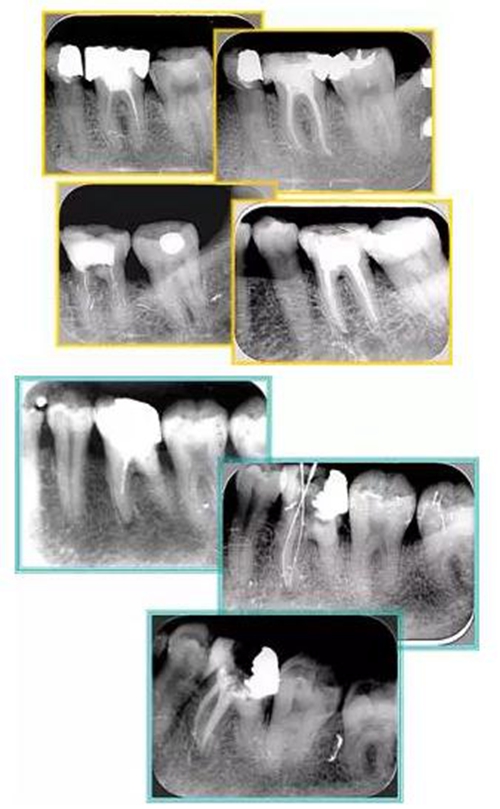

2. X 線片

共有 4 張 X 線片,分別是術(shù)前、診斷絲 、主牙膠尖確認(rèn)、術(shù)后。

( 1 )術(shù)前:術(shù)前 X 線片用來了解牙齒的大概情況。術(shù)前預(yù)期為多根牙時(shí) X 線片應(yīng)偏頭拍攝。

( 2 )診斷絲:根據(jù)術(shù)前 X 線片進(jìn)行開髓、根管的初步預(yù)備后,需要插入診斷絲,用來指示工作器械位置。常用 10 號(hào)或 15 號(hào)擴(kuò)大器作為診斷絲插入牙髓腔。

( 3 )主牙膠尖確認(rèn):通過術(shù)前預(yù)期和診斷絲診斷,明確工作長(zhǎng)度、牙根走向,進(jìn)行根管預(yù)備。之后應(yīng)進(jìn)行主牙膠尖(中銼)確認(rèn),已明確根管是否適合充填。

( 4 )術(shù)后:觀察治療效果。

6. 術(shù)后 X 線片

術(shù)后 X 線片用來評(píng)定根管充填 長(zhǎng)度、致密度(管壁清晰、側(cè)枝)等指標(biāo)。

15.jpg

左圖為根管充填術(shù)后 X 線片。圖中可見,根管充填較好。右下圖有白色小點(diǎn),為側(cè)方加壓導(dǎo)致糊劑擠出所致,表明根管充填比較致密。

多根牙時(shí)候需進(jìn)行偏移投照,正位投照無法說明具體哪根牙根管充填效果。